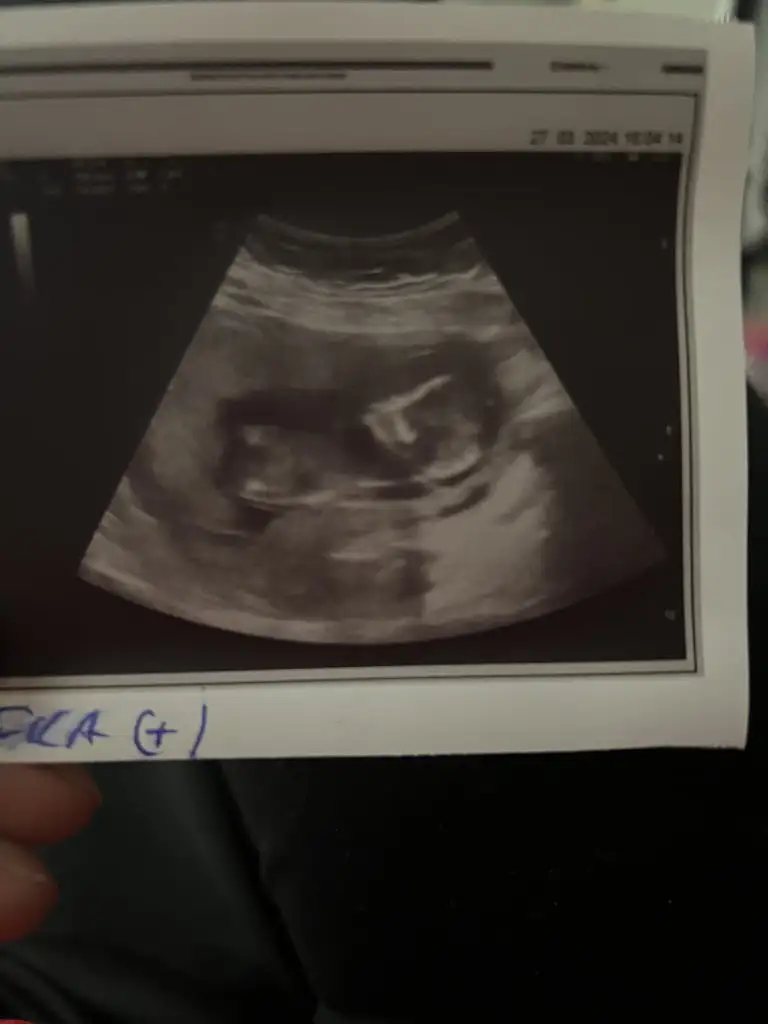

B Burrcu Aktif Üye Anneler Kulübü Kayıtlı Üye 5 Nisan 2021 377 599 53 36 Bodrum 8 Nisan 2024 Konu Sahibi Konu Sahibi angeller #26 Merhaba kızlar bizide tahminde bulunurmusumuz Eklentiler IMG_20240402_224309.webp 23,1 KB · Görüntüleme: 47